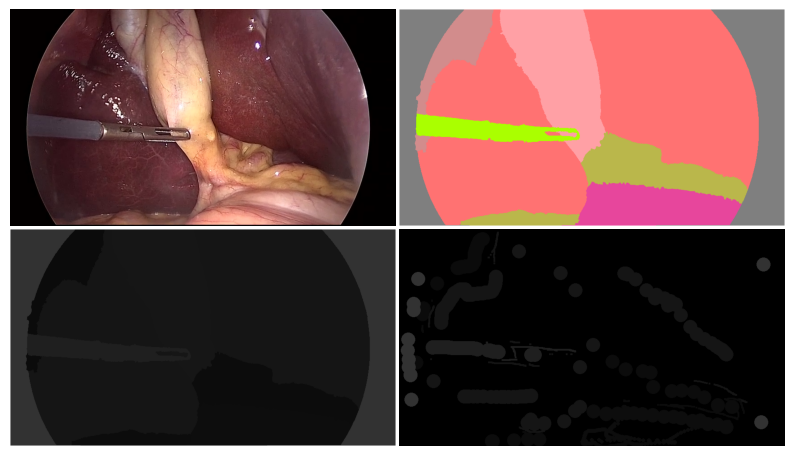

The CholecSeg8k dataset, an extension of the Cholec80 collection, includes 8,080 carefully annotated images from laparoscopic cholecystectomy surgeries, selected from 17 video clips in Cholec80. Each image in CholecSeg8K is pixel-level annotated for thirteen different surgical elements. The dataset is efficiently organized in a directory structure, featuring 101 folders, each containing 80 frames at a resolution of 854x480, along with three types of masks for each frame: a color mask for visualization, an annotation tool mask, and a watershed mask for simplified processing. This comprehensive dataset, freely available under the CC BY-NC-SA 4.0 license, is a critical resource for advancing the field of computer-assisted surgical procedures.

This short demo shows how to load the data and directly visualize an image along with the corresponding masks.

'''Display the image and corresponding three masks.'''

axs[0, 0].imshow(dataset['train'][image_index]['image'])

axs[0, 1].imshow(dataset['train'][image_index]['color_mask'])

axs[1, 0].imshow(dataset['train'][image_index]['watershed_mask'])

axs[1, 1].imshow(dataset['train'][image_index]['annotation_mask'])